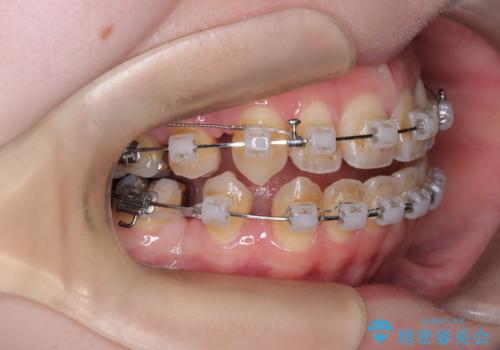

開咬・叢生(八重歯)を抜歯矯正で改善|ワイヤー矯正(クリア装置)症例

- ワイヤー矯正(クリア装置)

- 開咬と歯のデコボコ(叢生)、八重歯を主訴にご来院された患者様です。

矯正の精密検査の結果、上顎左右4番および下顎左右5番の計4本を抜歯し、ワイヤー矯正(クリア装置)にて治療を行いました。